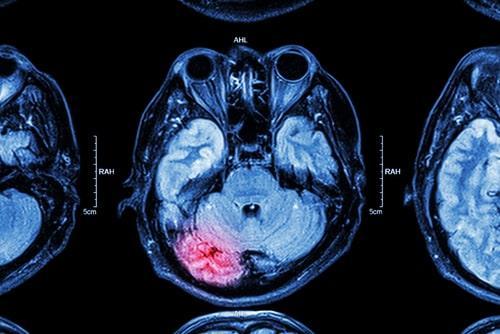

IL injury lawyerHead injuries are unlike other types of personal injury in that even a seemingly minor accident can have life-altering consequences. When a victim’s head is struck or moved in a violent or sudden manner, the brain may bump against the skull, causing severe injury. Brain injuries are often caused by car, truck, and motorcycle accidents, but they can also be caused by falls, workplace accidents, and more.

Types of Traumatic Brain Injuries

There are a few types of brain injuries that can be caused by an accident. Concussions are among the most common brain injuries. A concussion occurs when a force—such as an abruptly stopping vehicle—causes the head to violently accelerate and stop. Concussions can cause pain, blurred vision, confusion, memory loss, and nausea. Direct trauma brain injuries occur when a person’s skull comes into contact with a hard surface, such as during a slip and fall accident. Indirect trauma can be caused by whiplash, traffic accidents, and more. The resulting nerve damage from an injury such as this can cause brain damage and even death. A diffuse axonal injury occurs when the fibers which connect the brain and nerve cells are damaged. Brain injuries can also occur when the brain is deprived of oxygen. Exposure to toxic substances in an unsafe work environment is one-way hypoxia injuries occur.